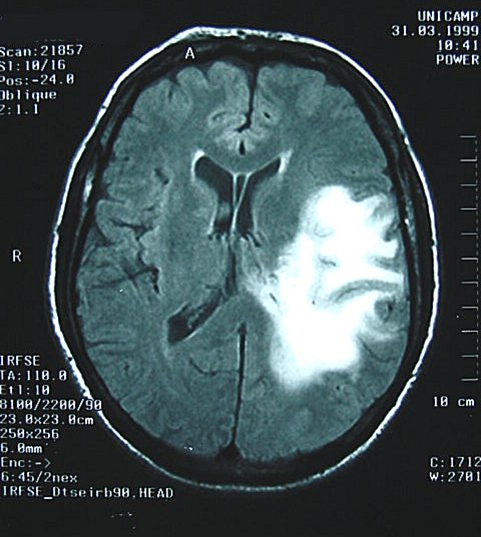

Lesiones cerebrales con melanoma con metastastasis y hemorragias

provocadas por metahemoglobina Fuente: anatpat.unicamp.br/Dsc33466+.jpg